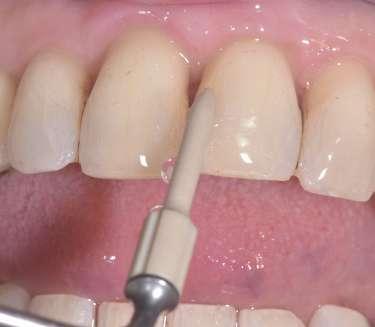

Consegnare l’allineatore invisibile con un kit dedicato alla cura dell’igienizzazione della mascherina è un momento importante di sensibilizzazione a corretti stili di vita. La terapia ortodontica con allineatori invisibili deve prevedere una particolare attenzione alla gestione dell’igienizzazione dello stesso, che deve consentire in maniera agevole di mantenere la trasparenza dell’allineatore ed assicurare l’efficacia nel contra-

stare inquinamento da batteri e virus. L’igienizzazione degli allineatori invisibili e degli apparecchi ortodontici mobili con ergonomici spray all’olio di oliva ozonizzato Ialozon clean (Gemavip) permette di mantenere la trasparenza del dispositivo ortodontico invisibile ed un più facile utilizzo nella fascia d’età adolescenziale. Al termine della terapia è fondamentale dopo il debonding, eseguire un clean-up ortodontico attento. Il Clean Up è l'innovativo approccio clinico che, grazie all’ausilio degli ultrasuoni e dell’inserto piezoelettrico D05120 con diamantatura D30 e dell’inserto D07102 con parte operativa in PEEK D06007 (MECTRON) permette la rimozione minimamente invasiva dei residui di adesivi e/o compositi a seguito di terapia ortodontica standard o invisibile. Il nuovo protocollo ENAMEL SAFE POST DEBONDING (G. M. Nardi et al.) “SMALTO SICURO POST DEBONDING” con tecnologia piezoelettrica si è dimostrato efficace e sicuro per il clean-up ortodontico. (Enamel Analysis by 3D Scanning after Three Orthodontic Clean- Up Procedures: An In-Vitro Test of a New Piezoelectric Tool).